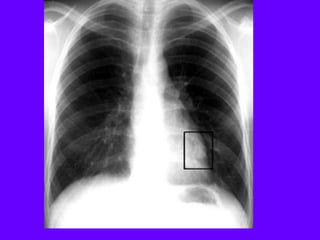

Pulmonary Metastsis

Colon in front of liver

Lymph Nodes